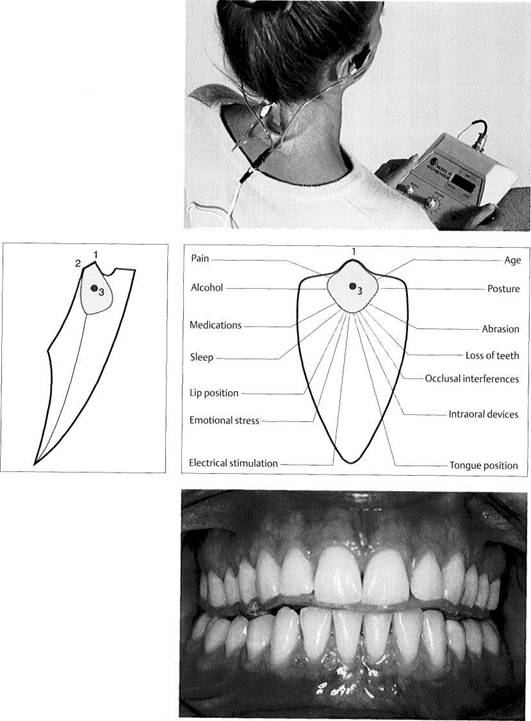

643 Marking the load-bearing and non-load-bearing cusps

Cusp ridges and cusp tips are marked with a pencil. The position of each cusp tip is also indicated by lines projected onto the buccal and lingual surfaces of the tooth.

Right: The lines reveal the positional relationships between the upper and lower buccal cusps in centric occlusion.

644 Outlining the abrasion facets

The outlines of the abrasion facets are traced with a sharp pencil. The direction of tooth-guided para-functional activities can be de­duced from the arrangement of the facets in relation to the individual functional structures of the teeth. A final differentiation of abraded sur­faces into active facets that are still brought into contact by the pa­tient, and inactive facets that no longer fit together can be made only through intraoral examination.

645 Marking centric occlusion

The condyles are locked in centric and the incisal pin is lowered. Then the centric occlusal contacts are marked with black articulating paper that marks on both sides.

Marking eccentric

occlusion

The centric set screws of the articu­lator joints are loosened. The dynamic occlusion is carefully checked with tooth-guided eccen­tric movements. The mediotrusive (nonworking), laterotrusive (work­ing), and protrusive contacts are marked with red articulating paper. Left: When the upper member of the articulator is guided properly, the mediotrusive condyle main­tains continuous contact with the Bennett guiding surface. In addi­tion, both condyles slide along the superior surfaces of the articulator housings.

Centric and eccentric

contact pattern on the maxillary

cast

The occlusal markings indicate in­adequate occlusal support in the posterior region. The eccentric guidance for the mandibular teeth is uneven and shows dominance in the molar region.

648 Occlusal contact pattern on the mandibular cast

Most of the eccentric contacts do not coincide with the outlined wear facets. This indicates that tooth-guided parafunctional movements also start from maximum intercus-pation.

Left: Sample from an examination form on which the current pattern of occlusal contacts can be docu­mented.